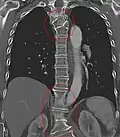

Congenital block vertebra in the lumbar spine (partial vertebrae 3 and 4). The rear portion of the disc still exists. -